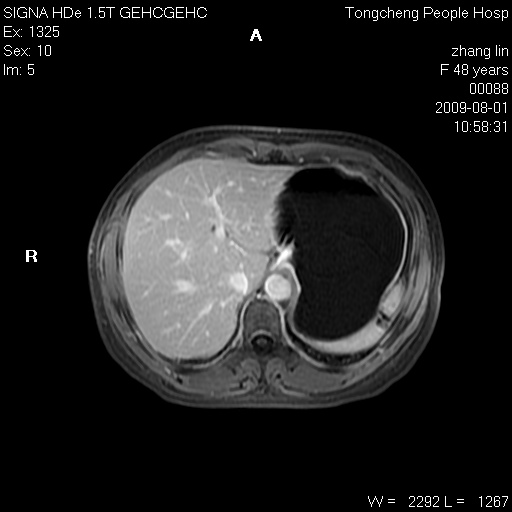

女,48岁。健康体检,彩超发现右肾占位性病变。平素健康。

临床诊断:右肾占位性病变,性质待定(囊肿?肿瘤?)。

上中腹部mr平扫+增强扫描,图像如下:

右肾上极见一类圆形病灶,t1wi呈等信号t2wi呈等高混杂信号,三期增强无强化,边界清---考虑囊肿出血。

同反相位均表现为等信号,病变无强化,考虑含蛋白的囊肿可能,弥散加权相或许有些帮助,

肝囊肿

慢性胆囊炎